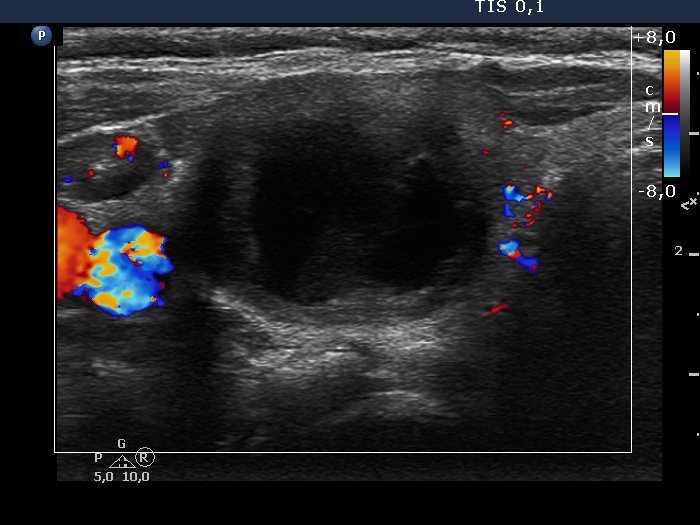

Intranodular hyperechogenic figures - case 372 (ultrasonographic picture 5)

Right lobe, transverse view, color Doppler mode. The vascularization is not specific.